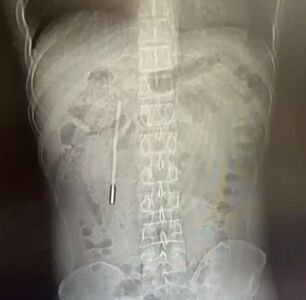

陸男12歲吞體溫計 32歲「消化不順」才想起​

浙江溫州一名32歲男子近日因腹消化不順就醫,醫生在他的體內發現一根體溫計,男子才想起,是自己12歲時吞下肚的,當時不敢告知父母,久了以後就忘了。